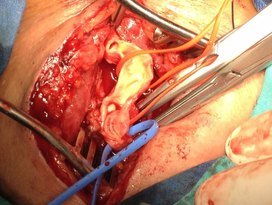

Boyuna karotis damar üzerindeki cildin 5cm'lik kısmına lokal anestezi uygulanır. Daha sonra 4-5cm'lil kesiden damara ulaşılır. Damar duvarı açılır ve damar içerisindeki plak çıkartılarak damar direk veya yama konularak kapatılır. Ortalama operasyon süresi 1.5-2 saat civarındadır.

Resim 1,2. Karotis endarterektomi (Karotis damar içerisinden plak çıkarımı)